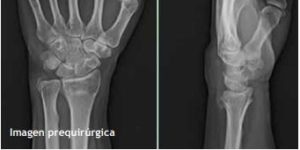

Caso 2.- Femenina de 64 años de edad. Un caso en el que, al control radiográfico de las cinco semanas, presentó una pérdida de la altura radial y el índice sagital, finalmente, sin ninguna repercusión clínica. (fig. 3)